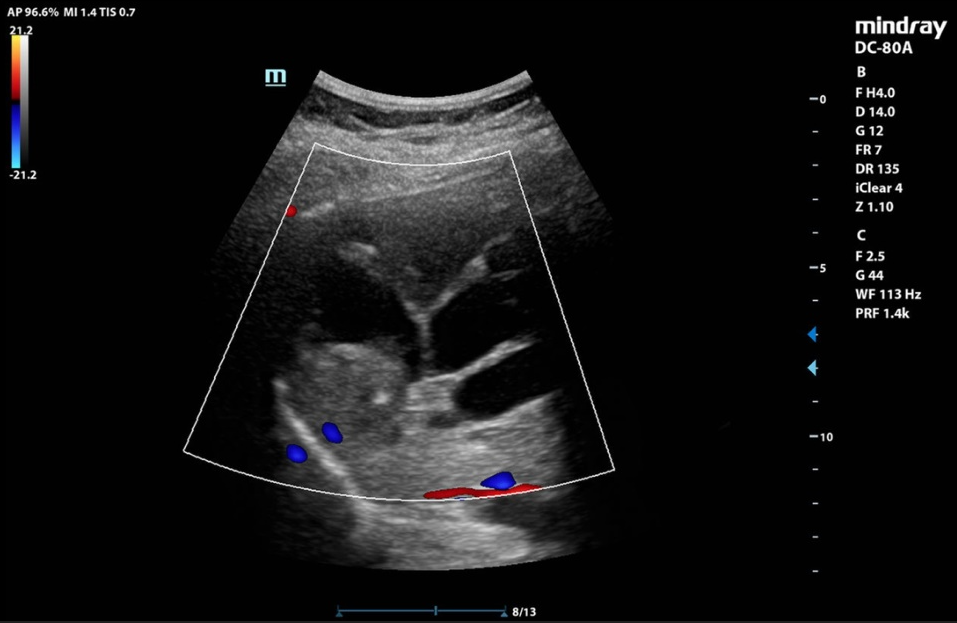

In der klinischen Untersuchung zeigt sich ein diskreter Sklerenikterus und ein leichter rechtsseitiger Oberbauchschmerz. Laborchemisch zeigen sich erhöhte Transaminasen sowie eine Bilirubinämie. Die Leukozyten und das C-reaktive Protein waren ebenfalls erhöht. In der orientierenden Sonographie bei dem Internisten zeigte sich eine ca. 16 cm messende echoarme, septierte Raumforderung, woraufhin die Patientin zur stationären Abklärung eingewiesen wurde. Bei der Aufnahme wurde eine Computertomographie des Abdomens durchgeführt.

In der CT-Untersuchung zeigte sich eine 16 x 14 cm messende, multilobulierte hypodense Raumforderung in den Lebersegmenten VII, VIII und VIa mit konsekutiver Cholestase im rechten Leberlappen. Die Pfortader und die Lebervenen waren offen. Die restlichen Organe waren unauffällig. Bei komplizierten Leberzysten wurde die Serologie für Echinokokkose abgenommen. Auf die gezielte Frage nach Kontakt zu Hunden und Füchsen hat Frau K. angegeben, dass sie drei Hunde auf dem Bauernhof hat. Der Echinokokken-IgG-Screening-ELISA war mit 47 U/ml positiv. Somit wurde die Diagnose einer Echinokokkose gestellt.